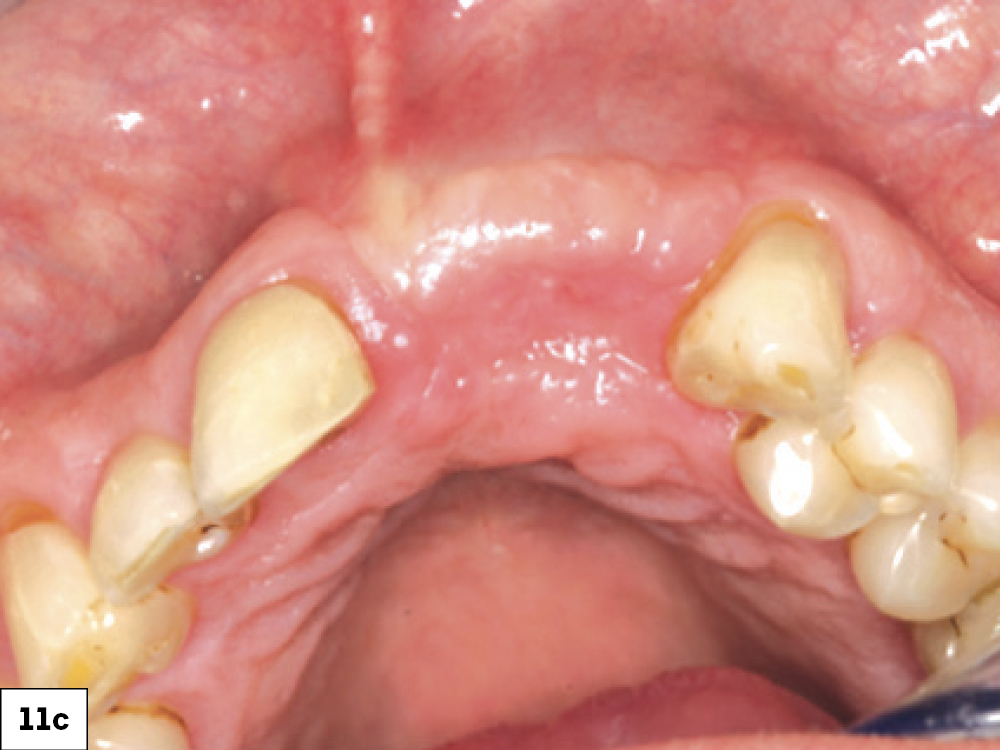

In most ILO cases, the correct treatment is to allow the surgical wound to heal via secondary intention. Allowing the site to heal by secondary intention requires considerable discipline and patient cooperation for a successful outcome (Box 2, Fig. 11). This treatment approach is influenced by various factors such as the health of existing tissue, tissue thickness, location, patient age and the size of the dehiscence. The technique involves implementing the following:

Successful healing by secondary intention: (a) two-week postop with ILO, (b) three-week post-op, (c) successful re-epithelization at four-week post-op.

Figures 11a–11c: Successful healing by secondary intention: (a) two-week post-op with ILO, (b) three-week post-op, (c) successful re-epithelization at four-week post-op.